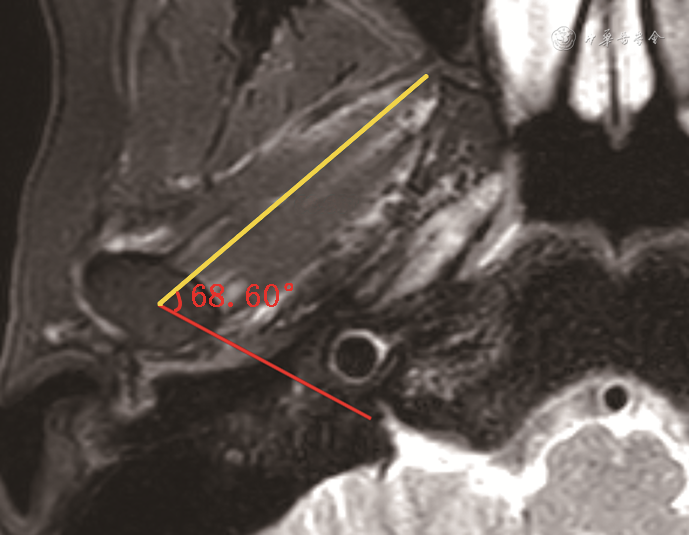

翼外肌与髁突的角度与关节盘侧向移位有关[15]。横轴位T2WI-FS图像测量经髁突长轴连线与同侧翼外肌下头长轴的交角(图4),角度增大可致关节盘向内侧移位,角度减小可致关节盘向外侧移位[15]。

注:黄线示经翼外肌下头长轴,红线示髁突长轴